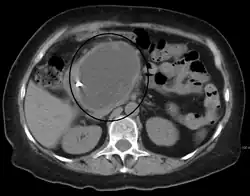

| A pancreatic pseudocyst as seen on CT | |

A pancreatic pseudocyst is a circumscribed collection of fluid rich in pancreatic enzymes, blood, and non-necrotic tissue, typically located in the lesser sac of the abdomen. Pancreatic pseudocysts are usually complications of pancreatitis,[5] although in children they frequently occur following abdominal trauma. Pancreatic pseudocysts account for approximately 75% of all pancreatic masses.[6]

The most useful imaging tools are:

- Computerized tomography[10] – this is the gold standard for initial assessment and follow-up.